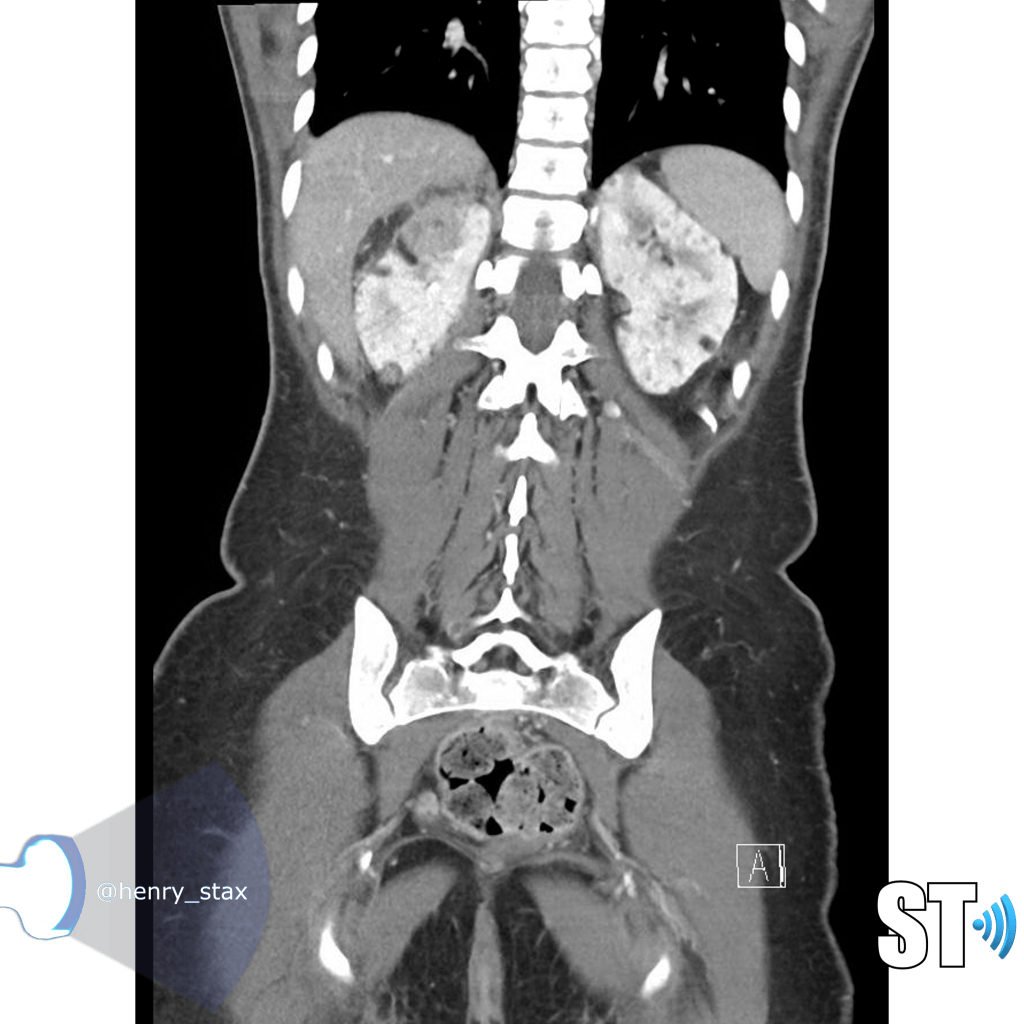

ADPKD

In Autosomal Dominant Polycystic Kidney Disease (ADPKD) the kidneys are normal at birth with cysts developing overtime. By age 30 years, approximately 68% of patients will have visible cysts by ultrasound. Eventually, virtually all patients develop cysts. The disease is transmitted in an autosomal dominant pattern, meaning you only one abnormal gene from one parent.

One abnormal gene from one parent

- Adult

- 4-10% of all cases of ESRF

- Kidneys appear normal early on

- Liver, pancreas and spleen cysts